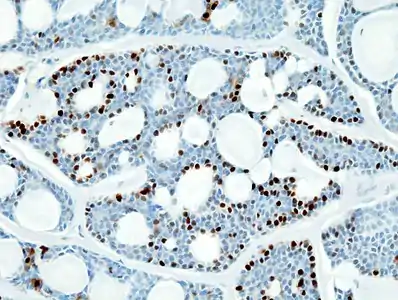

Histopathological image of adenoid cystic carcinoma of the salivary gland infiltrating a nerve (center), H&E stain

Histopathological image of adenoid cystic carcinoma of the salivary gland, immunostain for S-100 protein